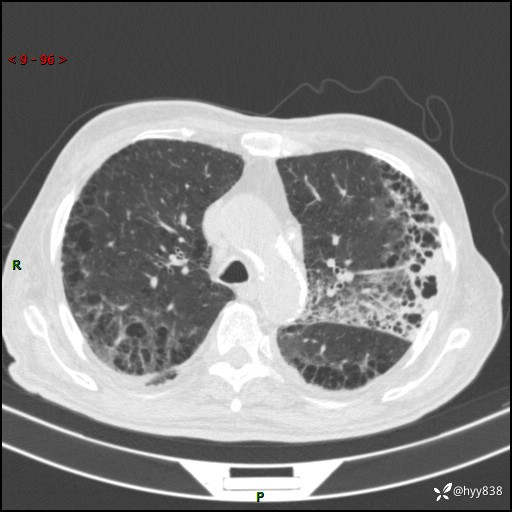

老年男性,间断咳嗽咳痰20余年,加重伴发热1天。呼吸科疑难病例讨论---结果公布

主诉:间断咳嗽咳痰20余年,加重伴发热1天

简要病史:家属代诉患者于20余年前无明显诱因出现咳嗽咳痰,痰为白色泡沫状,未行特殊治疗,不伴胸痛、胸闷、气喘、咳血等不适,1天前上午患者无明显出现发热,查体温39℃,伴咳嗽,咳痰无力,自行予以物理降温对症治疗,今晨2点左右再次出现发热,体温达40℃,自行服用复方氨酚烷胺对症治疗,凌晨3点左右复测体温38.2℃,现患者为求进一步诊治于今日就诊于我院门诊,行胸部CT提示双肺感染,遂以“肺部感染”收入我科。 患者本次起病来精神、食欲、睡眠欠佳,体力下降,体重无明显变化。

辅助检查:CT

胸部CT平扫